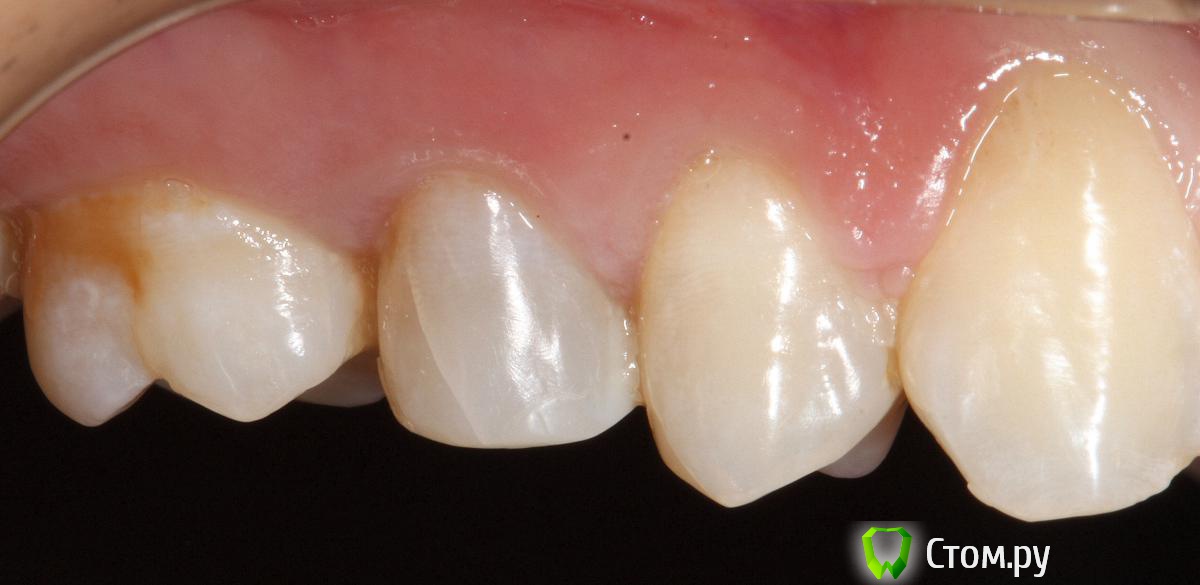

SDC Опубликовано 19 ноября, 2014 Поделиться Опубликовано 19 ноября, 2014 (изменено) Prettau, извините, не знаю, как редактировать название темы. Здравствуйте всем. В хирургическом много практиков, а по протетике - много теории)). Итак, разбавляю вино. (теория вечна)Протезирование премоляров коронками Преттау с нанесением керамики вестибулярно.Много фото, прошу прощения, поэтому без радикала, превью. Наверное даже так лучше, потому, что по клику откроются не сжатые фото, а радикал жмет.Протезирование в течение 2 недель. Фиксация на фуджи, без коффердама, но в сухих условиях (коффер не поставить по причине глубокий дистальной границы препарирования на обоих премолярах - глубокий кариес проксимальных поверхностей в анамнезе)Рг-контроль на предмет остатков цемента и на последнем фото удаленные излишки цемента на перчатке. Изменено 19 ноября, 2014 пользователем SDC 7 Ссылка на комментарий

SDC Опубликовано 20 ноября, 2014 Автор Поделиться Опубликовано 20 ноября, 2014 Отличный результат. Позвольте несколько вопросов.СВШ в боковых не ставите вообще,если да,то по какой причине?Как думаете антагонисты не будут истираться?Вы как-то меняете анатомию контакта при глубоких дефектах и недостатка сосочка?Спасибо.Спасибо Роман.По поводу штифтов. На самом деле, не имеет значения для меня.Важно, что не было титановых во фронтальном отделе (открываются при редукции тв.тк. небольшой объем композита вокруг штифта, что приводит к хрупкости билдапа и иногда металл.штифты светят через композит и керамику)Антагонисты истираться будут, а цирконий - нет. Что поделаешь.Сейчас мы с техником делаем нанесение вестибулярно и по скатам бугров, для уменьшения негативного эффекта повышенной прочности циркония и ускорения сдаваемости.контакт всегда площадочный, пятно контакта в корональной 1/4.Дефицит мягких тканей керамикой никогда не восполняем. Моделировка коронки максимально анатомична. Ссылка на комментарий